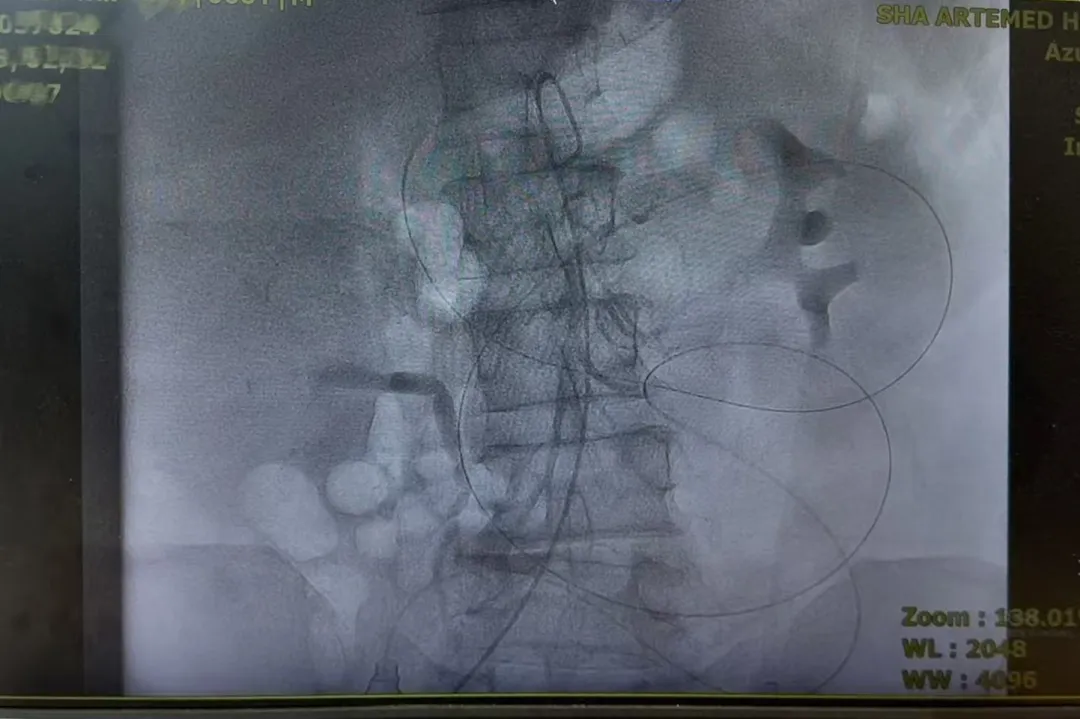

2025-10-112020年,全球的胃癌死亡病例为768793例[1],位居于所有癌症死亡谱的第四位,造成胃癌患者死亡的主要原因是复发和转移。其中,腹膜是胃癌最常见的转移部位,根据数据统计,70%的胃癌患者在手术后出现了腹膜转移[2],晚期胃癌的腹膜转移率可能更高。图片来源:freepik 胃癌是怎么转移到腹膜的呢?腹膜是腹腔里覆盖在腹壁内面和脏器外面的一层膜状组织,负责分泌黏液减轻内脏之间的相互摩擦,起着保护内脏的作用。腹膜本身就覆盖于胃的表面,胃壁的血管、淋巴管都经过腹膜与外界相连。因此,胃癌细胞能通过直接侵犯、血行转移、淋巴转移或种植途径到达腹膜,并在适宜的条件下“生根发芽”。由于胃壁的固有肌层中穿行着大量的淋巴管和血管,即使是早期的胃癌(T2期,侵犯固有肌层)也可能腹膜转移,多项回顾性研究中结论都表明:那些经过根治性治疗后却在短时间内出现转移的,很大一部分原因是在根治术之前没有发现已经存在的腹膜转移。图片来源:freepik胃癌腹膜转移如何早发现呢?早发现早治疗是所有疾病诊疗的最优解!对于腹膜转移的一些早期表现应该引起我们的足够重视!1、腹胀早期的腹膜转移一般不会出现明显的肿块,而会出现一些类如腹胀之类的非特异性表现,这时我们需要观察腹胀症状与饮食、排便、体位等的关系,如果是一过性出现的(如排便后缓解),则可能与消化不良等情况有关,如果持续不缓解、甚至进行性加重,则要引起高度重视,尽快就医检查。2、腹水在发生腹膜转移后,形成广泛的癌结节或腹腔游离癌细胞,影响腹膜本身的淋巴、血液运行,导致血管通透性增加、腹膜炎症发生、淋巴回流障碍以及低蛋白血症等,从而促进癌性腹水生成。据统计,由腹膜转移而引起的癌性腹水发生率高达90%,且预后不良,平均生存期仅12-20周[3]。不过,即使检查发现有少量腹水,也很难确认有没有腹膜转移,因为其他疾病也可能引起少量腹水(如低蛋白血症、腹膜炎症等)。 胃癌腹膜转移如何诊断呢?目前,确诊腹膜转移的方法有两种,一种是腹腔灌洗液/腹水的细胞学检查,一种是诊断性腹腔镜探查。很多腹膜转移是在准备进行胃癌根治术前,通过腹腔镜探查发现的。根据检查结果,腹膜转移又被分为“腹腔游离癌细胞阳性”和“肉眼可见腹膜转移”两种类型。图片来源:freepik1、腹腔游离癌细胞阳性:就是在腹腔灌洗液、腹水等检查中找到了胃癌细胞,但没有发现肉眼可见的腹膜转移灶结节。2、肉眼可见腹膜转移:腹腔镜或者影像学明确腹膜转移灶,如CT发现腹膜上呈饼状的结节,增强后明显强化,可伴有腹水四 胃癌腹膜转移如何治疗呢?随着肿瘤治疗理念的进步,很多单一转移或寡转移的病灶可以通过转化治疗等新的治疗方式来取得临床治愈的效果,例如结直肠癌肠癌单一肝转移等。但在腹膜转移中,由于腹膜范围广泛、局部处理难度极大,因此很难将腹膜转移视为单一部位转移,手术治疗仅在少数患者中进行且争议较大。针对不同的腹膜转移类型,进行分层管理诊疗,是目前胃癌腹膜转移的主要治疗手段,包括腹腔化疗港置入、腹腔热灌注及新辅助/转化治疗等,明确改善了患者预后。图片来源:freepik1、仅有腹腔游离癌细胞阳性(CY1P0)就是在完善检查后,只发现腹腔游离癌细胞阳性,没有肉眼可见的转移灶。从技术上来说,CY1P0的腹膜转移是可以做根治性切除的。不过,人们发现单纯切除腹膜并不能提高这部分患者的生存率(生物学上不可切除)。因此,目前CY1P0的治疗仍是以系统性为基础,原发灶(胃)手术联合前/中/后腹腔热/灌注/化疗等综合治疗模式。术前治疗:Meta分析结果显示,共计6499例胃癌腹膜转移患者中,进行术前治疗并在术前腹腔细胞学转为阴性的患者的生存时间明显延长,术前治疗包括化疗、腹腔灌注等[4]。手术治疗:除非有明显的局部症状(出血、疼痛等),考虑到腹膜切除的难度,一般CY1P0的手术只有在腹腔细胞学完全转阴后才做考虑。术中腹腔灌注:就是把化疗药直接灌倒腹腔内,通过与腹膜充分接触发挥细胞毒作用。荟萃分析显示,手术联合腹腔化疗/广泛灌洗可以提高5年生存率、降低复发率。术后治疗:CCOG0301研究指出[5]:CY1P0术后替吉奥单药辅助化疗,患者的平均生存时间达22.3个月。 2、仅有肉眼腹膜转移(P1)单纯肉眼腹膜转移的患者,就算是化疗起到缩小转移灶的效果,手术完全切掉肉眼转移灶后,仍然有大部分人出现腹腔内复发。因此,对于P1胃癌的治疗,以全身治疗(化疗)为主,配合腹腔灌注治疗。只有在腹膜转移灶化疗效果好时,才考虑手术治疗,这种手术又被称为“肿瘤细胞减灭术”。研究显示:化疗后进行肿瘤细胞减灭术的患者生存时间长于没有手术者。 3、肉眼腹膜转移伴其他脏器转移以姑息性治疗为主,对有腹胀、腹水等症状的腹膜转移,可以考虑腹腔灌注及腹水引流,局部症状严重(如出血、梗阻等)时可以考虑姑息性手术治疗。只有极少数经过严格筛选的、对转化化疗反应好的患者有可能获得根治性切除的机会。 文末小结胃癌一旦发生腹膜转移,理论上来说就已经属于晚期了,其治疗还是应该以全身性药物治疗为基石、腹腔局部治疗为补充,手术治疗需要经过医生严格的评估后才考虑。参考文献:[1]闫超,陕飞,李子禹.2020年全球胃癌负担分析:聚焦中国流行现状[J],中国肿瘤.2023,32(03):161-170.[2]预防性腹腔热灌注治疗应用于进展期胃癌术后的研究进展[J],世界最新医学信息文摘.2020,20(85):109-111.[3]金春英,荆丽莉.腹腔热灌注化疗联合静脉化疗治疗胃癌性恶性腹水的临床疗效分析[J],临床研究.2017,15(18):160.[4]张俊.胃癌腹膜转移诊治的立与破[R].北京:2024CSCO胃癌专家委员会学术年会,2024.[5]CCOG0301研究组.单纯腹腔游离细胞学阳性的胃癌患者行常规D2手术及术后辅助S-1化疗的Ⅱ期单臂研究[R].北京:中国临床肿瘤学会,2015.